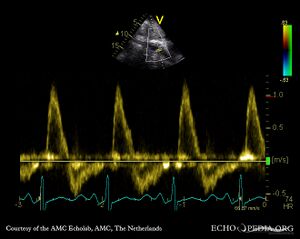

Subcostal view: flow reversal in abdominal aorta